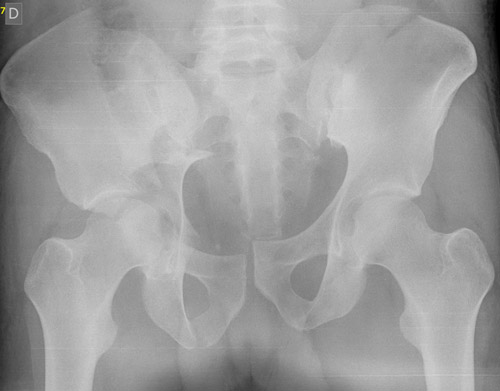

Pre-op X-Rays after applying correct amount of binder compression

Pre-op X-Rays